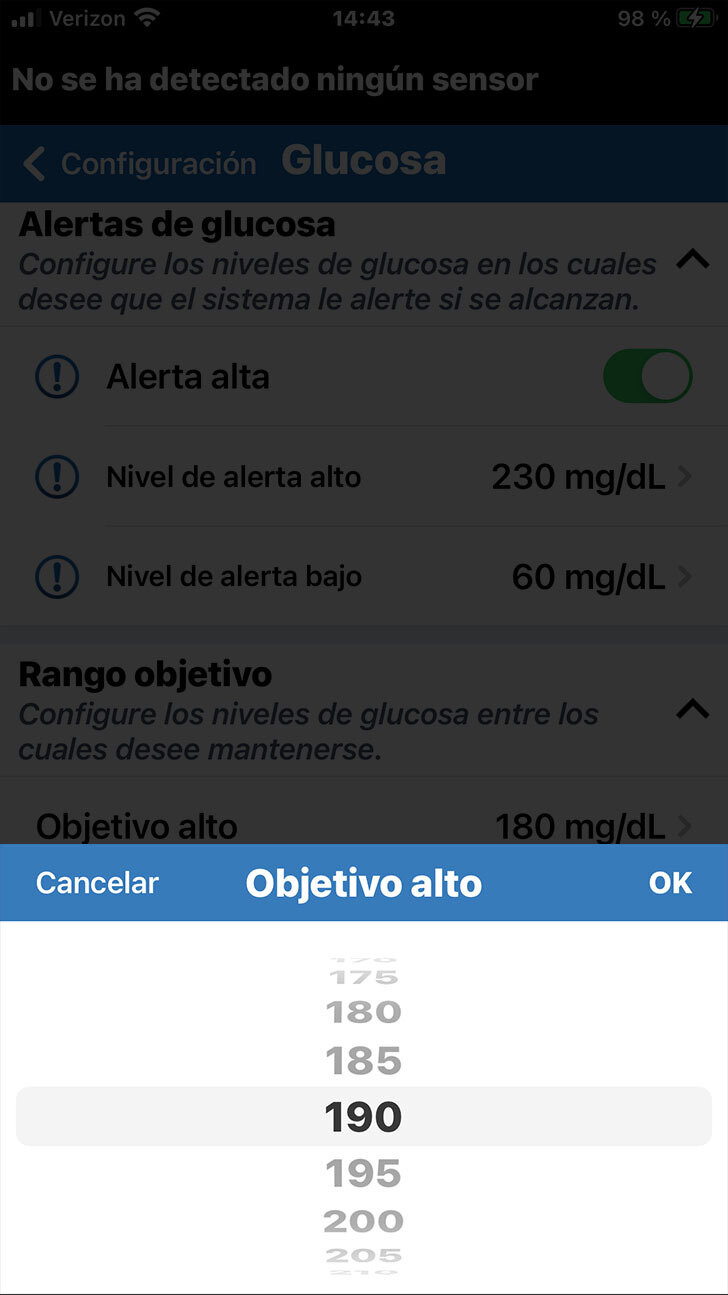

Debajo de Alertas de glucosa puede configurar su Intervalo objetivo de glucosa.

El intervalo objetivo de glucosa es la zona en la que tanto usted como el profesional de la salud deciden que deben estar sus niveles de glucosa la mayor parte del tiempo.

PERSONALICE LOS OBJETIVOS DE GLUCOSA

PERSONALICE LOS OBJETIVOS DE GLUCOSA

Nuevamente, solo tiene que tocar en el ajuste que le gustaría modificar, desplazarse hasta al valor deseado y, finalmente, tocar OK.

Debajo de Alertas de glucosa puede configurar su Intervalo objetivo de glucosa.

El intervalo objetivo de glucosa es la zona en la que tanto usted como el profesional de la salud deciden que deben estar sus niveles de glucosa la mayor parte del tiempo.

Tenga en cuenta que los niveles objetivo

de glucosa solo se pueden programar dentro de los niveles de alertas

de glucosa que ha definido.

PERSONALICE LOS OBJETIVOS DE GLUCOSA

Nuevamente, solo tiene que tocar en el ajuste que le gustaría modificar, desplazarse hasta al valor deseado y, finalmente, tocar OK.